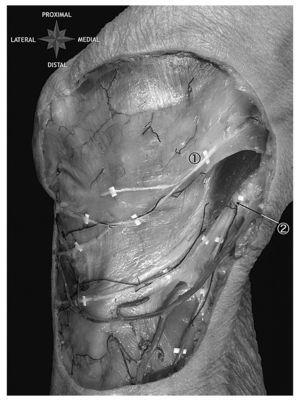

Estudios anatómicos sobre la distribución de la inervación rotuliana ponen en evidencia una importante variabilidad a nivel del borde medial y, sobre todo, en el borde lateral de la rótula1,2. A nivel medial la inervación depende del nervio safeno interno, una de las ramas principales del nervio crural. El nervio safeno interno tiene un trayecto final variable, pudiéndose observar tres ramas: la accesoria arterial o superficial (presente en el 20% de los especímenes), la accesoria venosa o retromuscular (en el 60% de los casos) e infrarrotuliana o profunda (en el 20% de los casos) (fig. 2). En el borde lateral de la rótula la variabilidad anató-mica es aún mayor. En el margen látero-inferior de la rótula no se ha encontrado una inervación específica, mientras que en la mitad superior parece ser que ésta puede depender de dos ramas: la articular del nervio del músculo vasto externo (rama del nervio cuádriceps que depende a su vez del nervio crural) y el plexo rotuliano (plexo nervioso formado por la unión de ramas terminales del nervio musculocutáneo externo y del nervio safeno interno, ambos ramas del nervio crural). Debido a esta alta variabilidad anatómica, una neurotomía selectiva no conduce en la mayoría de las ocasiones a una desensibilización rotuliana3. Por ello parece más lógico conseguir esta denervación lesionando los receptores del dolor que se encuentran localizados a nivel del tejido perirrotuliano, como indican los estudios de Wotjys5.

Figura 2.Disección anatómica de la región anterior de la rodilla. Se observa la inervación profunda de la región anterior de la rodilla con la rama infrarrotuliana del nervio safeno interno (1) y una rama accesoria infrarrotuliana (2).